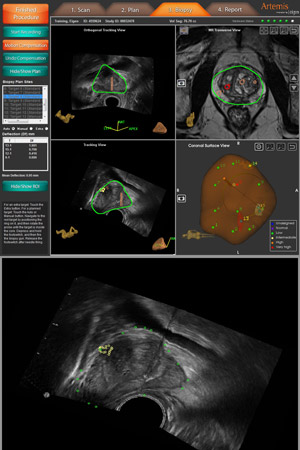

Das Artemis-System

MRI-Sonographie fusionierte Biopsie

Dabei können tumorsuspekte Areale direkt abgebildet und markiert werden. Diese Areale werden nun mit dem hochmodernen Artemis-System direkt punktiert.

Die MRI Bilder werden dabei mit dem Ultraschallgerät direkt fusioniert und so kann der Urologe die tumorverdächtigen Areale gezielt punktieren und Gewebe entnehmen.

Da die MRI-Diagnostik eine genau Differenzierung der Prostata erlaubt, werden durch das Artemis-System unnötige und ungezielte Biopsien verhindert.